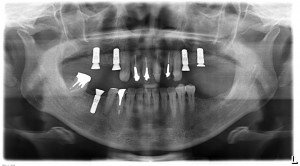

蓑毛_祇20161215_24688

術後のレントゲンです。